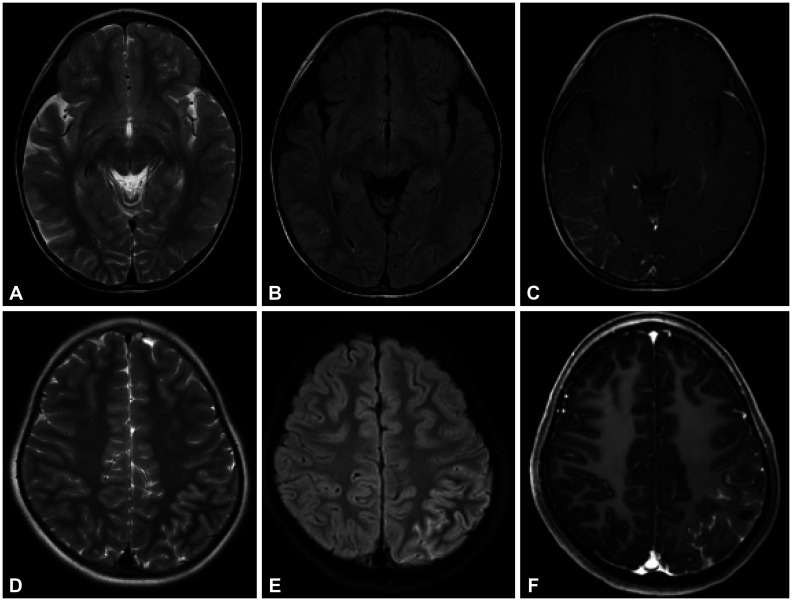

Results: The median age at onset was 7 years (range 2-16 years). The median number of relapses was 2 (range 1-8), and patients were followed up for a median of 65 months (range 5-214 months). The first relapse was experienced before 3 months from onset by 15 patients (34.9%). The most-common initial phenotypes were acute disseminated encephalomyelitis (n=17, 39.5%) and optic neuritis (ON; n=11, 25.6%). The most-common relapse phenotypes were neuromyelitis optica spectrum disorder (n=9, 20.9%), relapsing ON (n=6, 14.0%), and multiphasic disseminated encephalomyelitis (n=6, 14.0%). Many of the patients (n=18, 41.9%) were not specifically categorized. A high proportion of these patients had non-acute disseminated encephalomyelitis encephalitis. Atypical phenotypes such as prolonged fever or hemiplegic migraine-like episodes were also noted. Mycophenolate mofetil and cyclic immunoglobulin treatment significantly reduced the annual relapse rates.